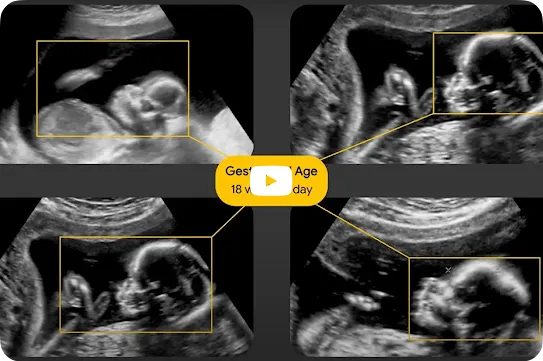

Obstetric ultrasound is necessary to optimize the health of birthing people and their babies, yet it remains unavailable to half of pregnancies worldwide. By developing tools using AI technology to highlight health risks, we hope to make the benefits of ultrasound available to more pregnant people, even when trained operators are not accessible.